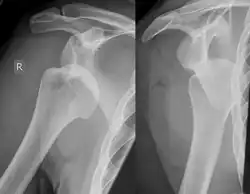

Hill–Sachs lesion post-shoulder dislocation

X-ray at left shows anterior dislocation in a young man after trying to get up from his bed. X-ray at right shows same shoulder after reduction and internal rotation, revealing both a Bankart lesion and a Hill-Sachs lesion.